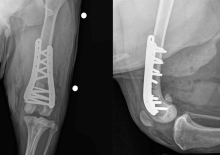

They cut the femur above the knee to realign the bone, and added an implant to correct its shape. They also reshaped the groove in which the kneecap glides to make it more difficult for it to slide out of position.

Six months after a successful surgery on the left leg, the team repeated the procedure on the right.